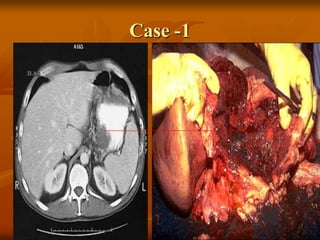

 A, A cross-section through the head of the pancreas and

adjacent common bile duct showing both an ill-defined

mass in the pancreatic substance (arrowheads) and the

green discoloration of the duct resulting from total

obstruction of bile flow.

 B, Poorly formed glands are present in densely fibrotic

stroma within the pancreatic substance; there are some

inflammatory cells